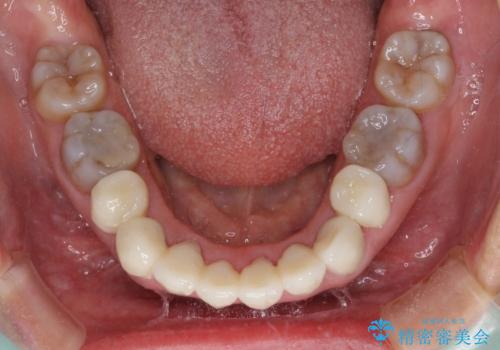

気になる変色歯を仮歯に変え、その後歯列不正を矯正治療で改善し、最後にオールセラミッククラウンにて補綴治療することとしました。

数十年に及んだ歯の変色が改善されたため、大変満足していただきました。